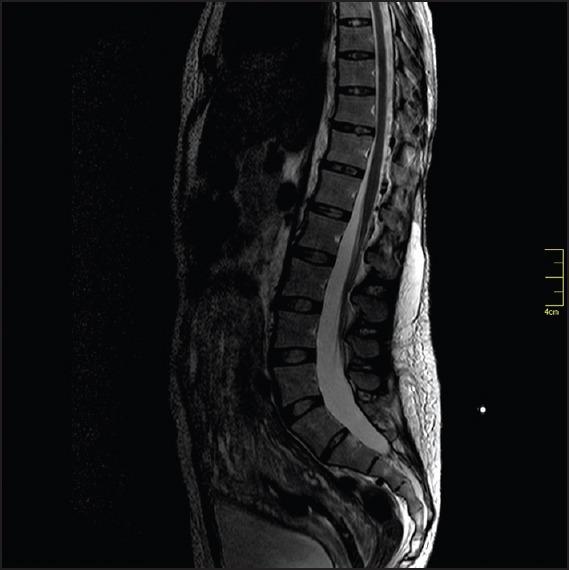

Epidural blood patch (EBP) is the currently accepted treatment of choice for postdural puncture headache because of its high initial success rates and infrequent complications. Many authors recommended a small volume (10-20 mL) of blood to be delivered for an effective EBP. Here, we report an obstetric patient who developed a transient bladder and fecal incontinence after 19 mL of blood EBP at L1 -L2 level. Since the magnetic resonance image did not demonstrate any definitive spinal cord lesion, the exact mechanism remains unclear. We suggest that accumulation of blood performed at L1 to L2 level in a closed relationship with the sacral cord, may have trigger a significant pressure elevation of the epidural space at this level, resulting in a temporal spinal cord-related injury in the sacral cord.

硬膜外血贴疗法(EBP)因其较高的初始成功率和较少的并发症,是目前公认的治疗硬膜穿刺后头痛的首选方法。许多作者建议注入少量(10-20毫升)血液以进行有效的硬膜外血贴疗法。在此,我们报告一例产科患者,在L1-L2水平注入19毫升血液进行硬膜外血贴疗法后出现短暂性膀胱和大便失禁。由于磁共振成像未显示任何明确的脊髓病变,确切机制尚不清楚。我们认为,在与骶髓密切相关的L1至L2水平进行血液积聚,可能引发该水平硬膜外间隙压力显著升高,导致骶髓出现与脊髓相关的暂时性损伤。